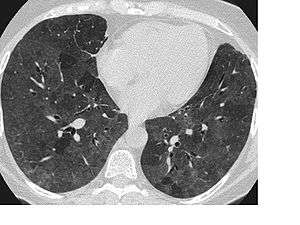

Signs and symptoms of flock worker's lung include rales (crackling noises caused by fluid in the lungs), dyspnea (shortness of breath), and coughing. Abnormalities seen on a computed tomography (CT) scan of the lungs can include ground glass opacity and reticular opacity. The typical histopathology in flock worker's lung is bronchiolocentric interstitial pneumonitis and lymphocytic bronchiolitis with lymphocytic hyperplasia. Occasionally, desquamative interstitial pneumonia and bronchiolitis obliterans organizing pneumonia can be seen.[3][4]

A CT scan of the lungs and histopathology along with a history of working in the flocking industry can diagnose flock worker's lung. A differential diagnosis may also include Sjögren's syndrome and lymphoid interstitial pneumonia.[3] Flock worker's lung may be misdiagnosed as asthma or recurrent pneumonia.[7] Though X-rays may be abnormal, CT scans are more useful as a diagnostic tool in flock worker's lung.[5] Other diagnostic methods may include a transbronchial biopsy or wedge biopsy.[7]